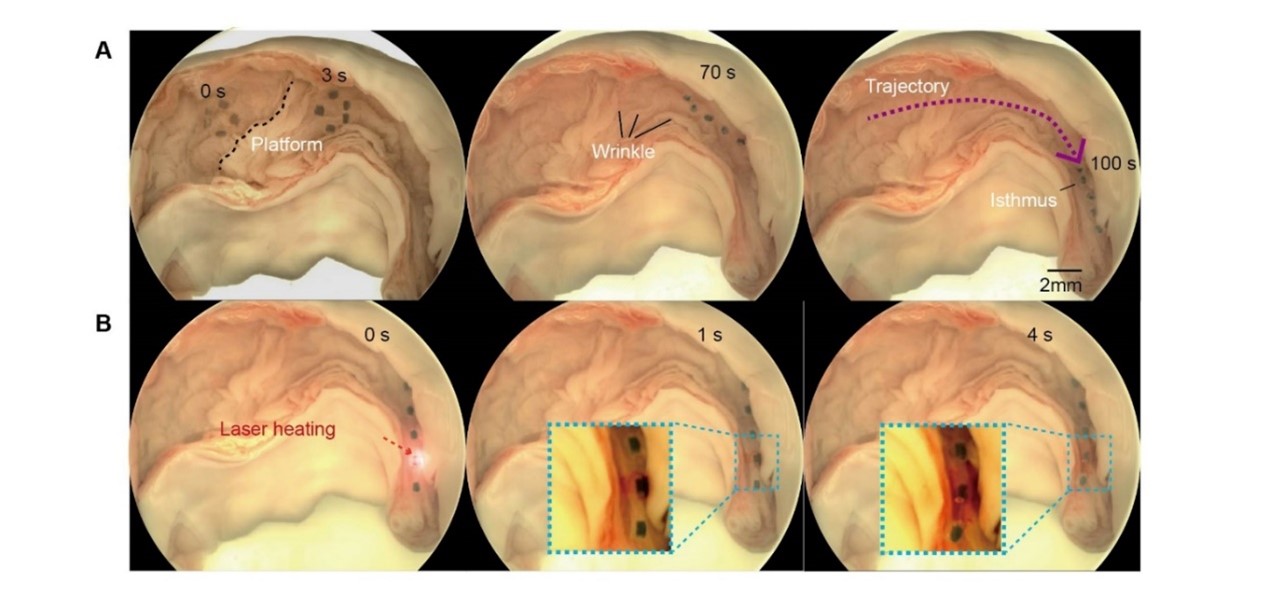

通过在离体猪输卵管中控制微型软体机器人执行自适应多模态运动和药物递送,以证明微型机器人在真实小腔道中的适用性。离体输卵管提供了真实的生理环境,具有各种类型的屏障,包括平坦区域、皱纹、粘液层和狭窄通道。在磁场下,微型机器人朝着目标区域前进,在100秒内运动了55mm,在目标区域快速释放药物,展示了其对输卵管环境的适应性。离体器官实验的成功验证了微型机器人对于这一特定应用场景的适用性,验证了微型软体机器人通过局部区域内生物货物释放以治疗女性上生殖道疾病(例如肿瘤、粘连、感染和炎症)的潜力。未来可对其结构几何形状进行改进,以提高其在各种医疗场景中的多功能性。这种体内跨尺度的机器人转运系统无需穿刺或设备干预,为体内的药物和细胞等生物样本递送提供了一种安全、高效的方式。

图2 演示微型软体机器人在猪输卵管中的主动药物输送。 (A) 和激光诱导(热响应)药物释放 (B)在离体猪输卵管中进行三次重复,以实现适应性多模态运动和药物递送。